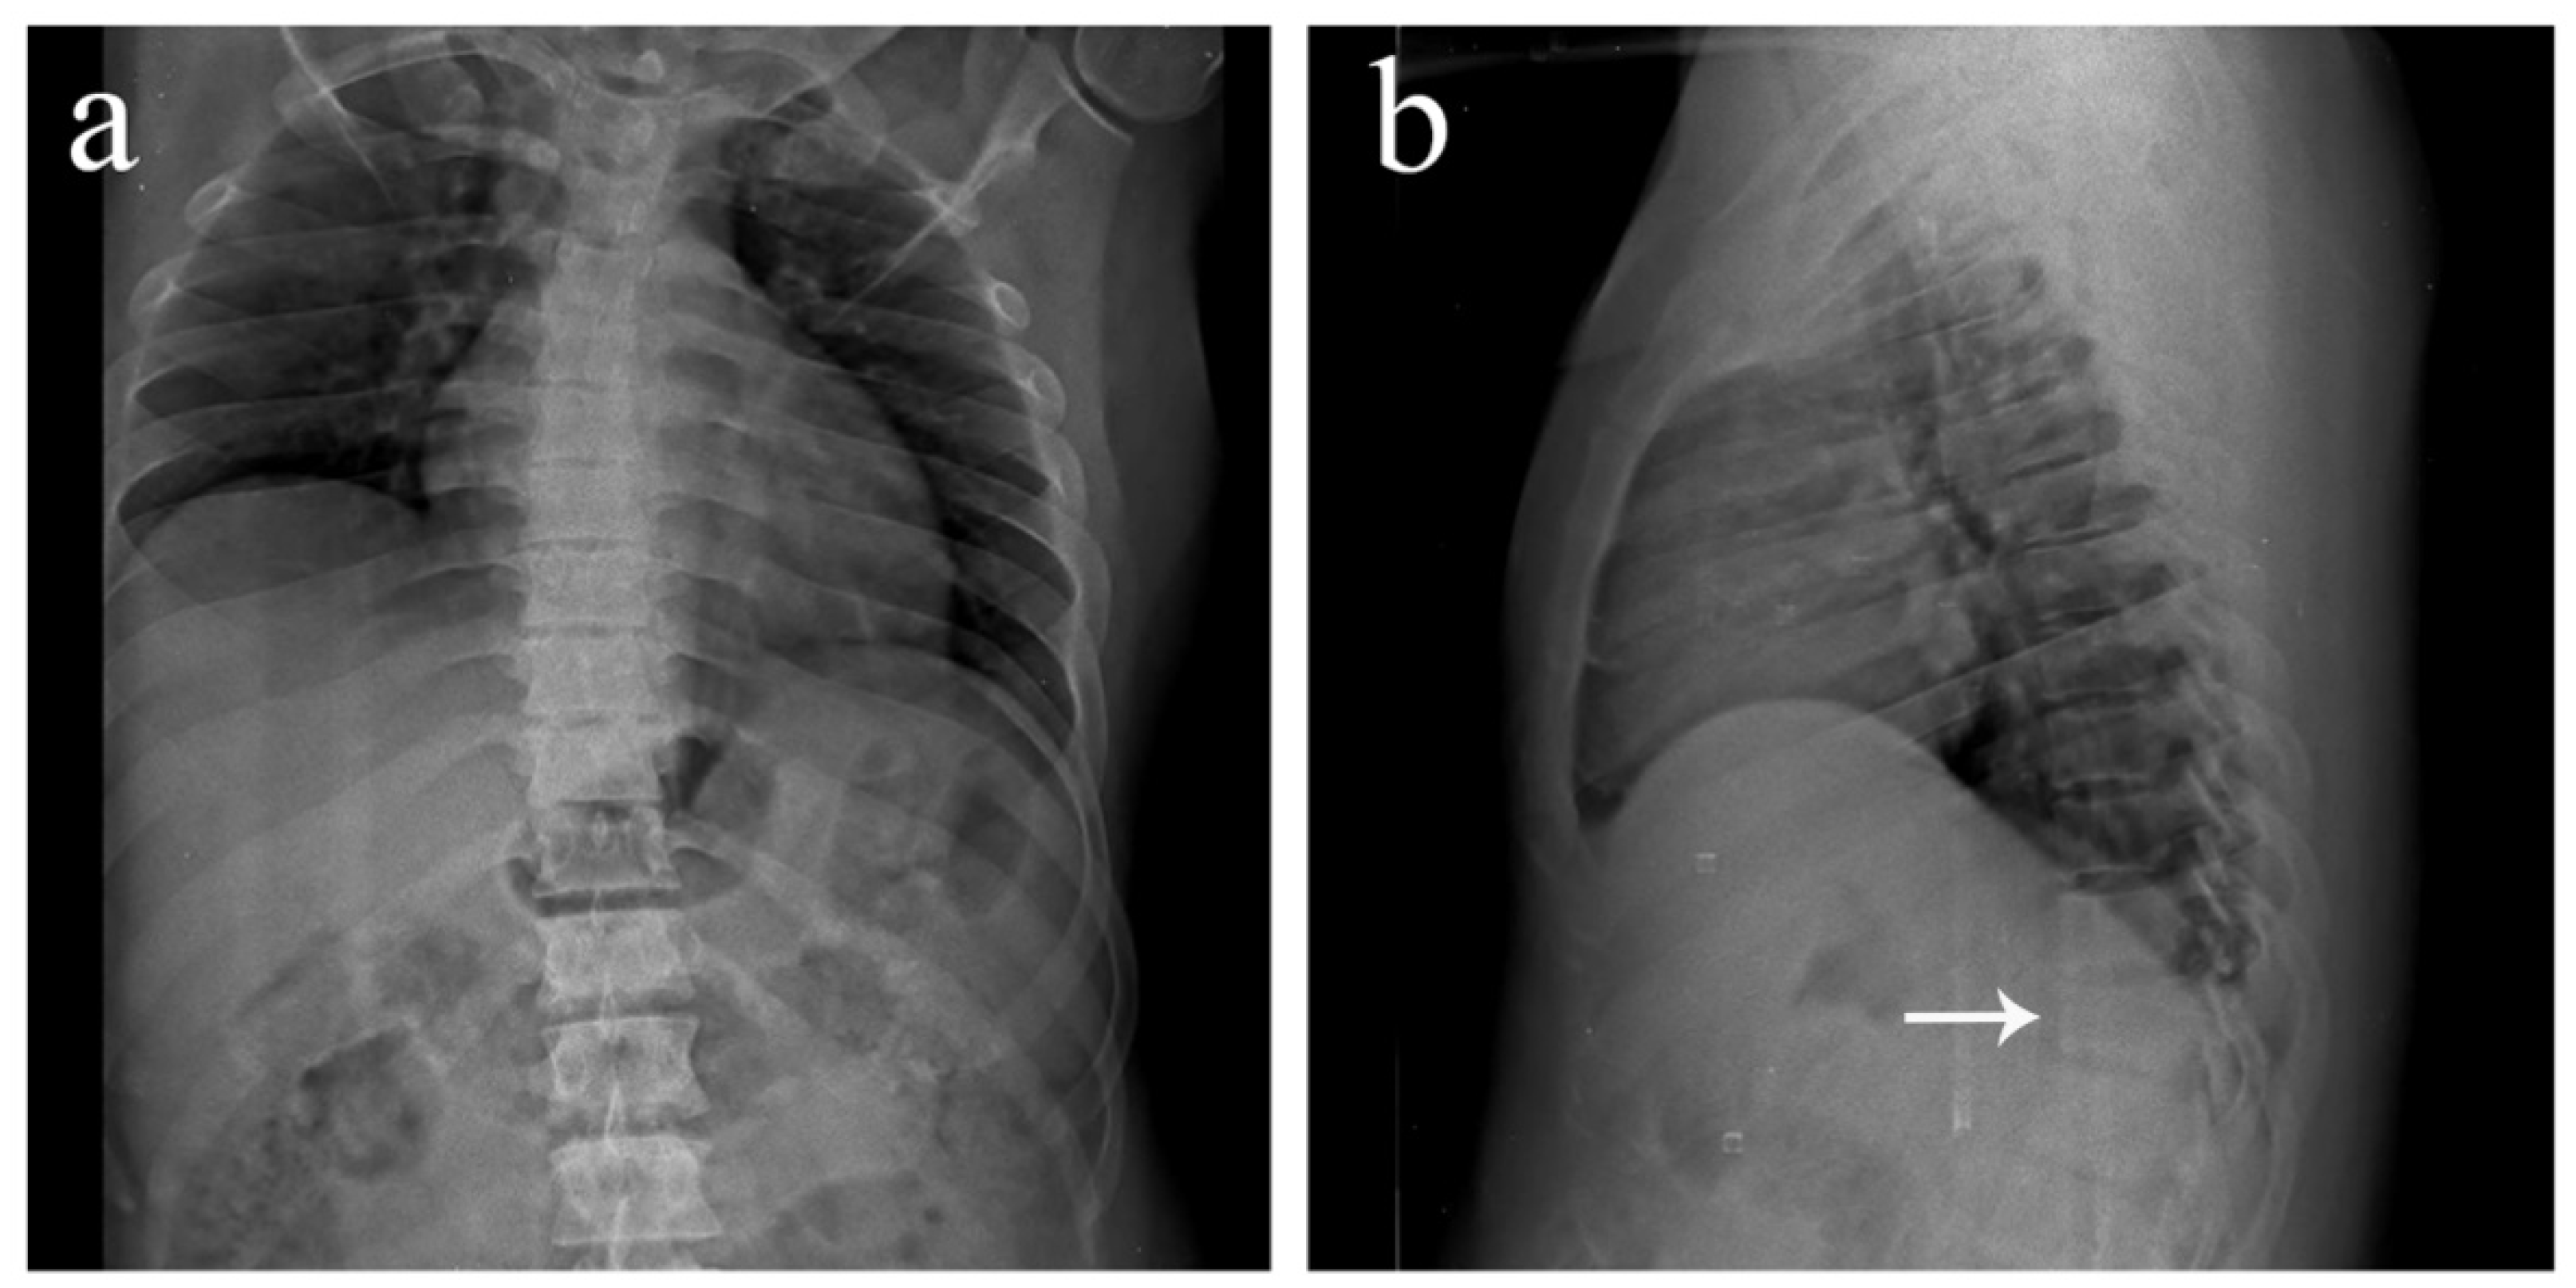

Figure 1. Antero-posterior and lateral view plain radiographs of a 35-year-old male who was brought to the emergency department with multiple abrasions over the trunk and pain in the upper back following a motor vehicle accident. He was conscious and well oriented with stable vitals. Upon examination, midline tenderness was elicited throughout his upper back. His motor power was 5/5 in all four limbs, and there was no sensory deficit. Plain radiographs revealed an obvious anterior wedge compression fracture of the T11 thoracic vertebra. However, since tenderness was elicited throughout the upper thoracic spine and not confined just to the T11 level, more fractures were suspected. On further examination of the anteroposterior view radiograph, it was noticed that the spinous process shadows of the upper thoracic vertebra were either absent or deviated. This brought suspicion of multiple spinous process fractures, which were later confirmed using a computed tomography (CT) scan. (a) Antero-posterior view of the thoracic spine showing absent or deviated spinous process shadows throughout the upper thoracic spine, raising suspicion of spinous process fractures. (b) Lateral view of the thoracic spine showing a compression fracture of T11 vertebrae (arrow). (c) Antero-posterior view of the lumbar spine where the T11 vertebra appears to be sclerotic (arrow). (d) Lateral view of the lumbar spine showing normal lordosis and the T11 compression fracture (arrow).